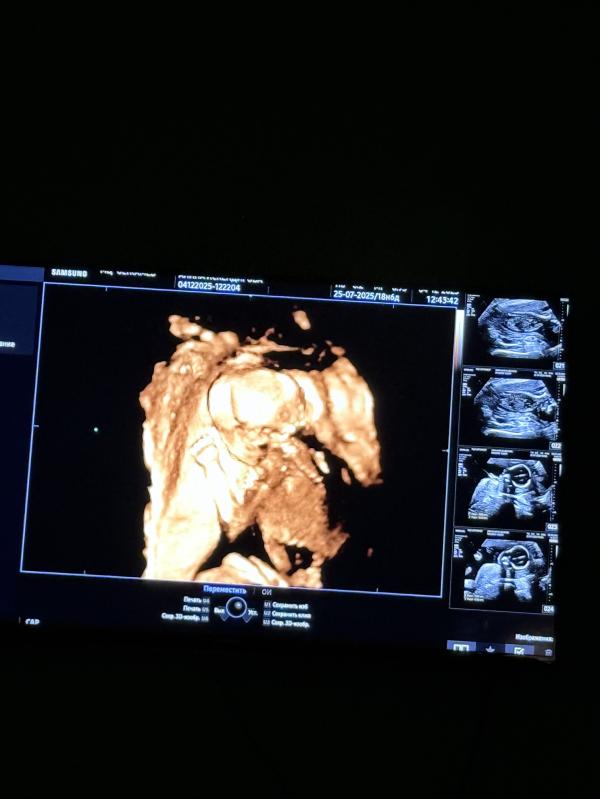

Второй скрининг беременности: как прошло и что показал

Вышла со 2 скрининга

Аллага Шукир все хорошо с дочей 🤲🏻